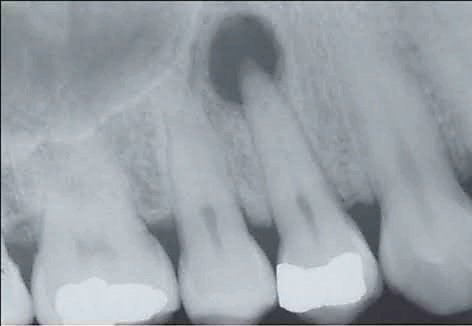

- Un bilan radiologique : panoramique dentaire au minimum, cone beam si nécessaire.

Erreur 3 — Négliger le bilan radiologique complet

Le problème : un simple examen clinique peut ne pas révéler des lésions apicales silencieuses, notamment en cas de dents dévitalisées anciennes asymptomatiques. Ces foyers « dormants » sont pourtant actifs sur le plan bactériémique.

La bonne pratique : systématiser la réalisation d’un panoramique dentaire complet chez tout patient adressé pour bilan stomatologique, complété au besoin par un cone beam ciblé.

Problématique identifiée : les hémocultures reviennent positives à Streptococcus viridans — un streptocoque d’origine buccale. L’examen stomatologique révèle une dent dévitalisée en secteur 26, traitée il y a 12 ans, présentant à la radiographie un large granulome apical asymptomatique.

Un granulome apical peut-il être asymptomatique et quand même provoquer des manifestations à distance ? Oui, c’est même le cas le plus fréquent. Les granulomes apicaux chroniques sont souvent totalement indolores car l’organisme a établi un équilibre avec le foyer infectieux. Ils peuvent néanmoins entretenir une bactériémie de bas grade et des réactions inflammatoires ou allergiques à distance. Seul le bilan radiologique permet de les détecter.